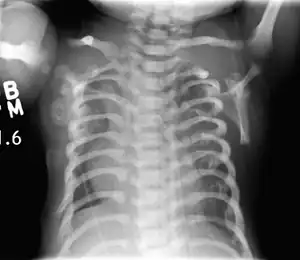

| CXR of a newborn with asphyxiating thoracic dysplasia. Note the short ribs. | |

Jeune syndrome is a rare genetic disorder that affects the way a child’s cartilage and bones develop. It begins before the child is born and primarily affects the child's rib cage, pelvis, arms and legs.[6] Usually, problems with the rib cage cause the most serious health problems for children with Jeune syndrome. Their rib cages (thorax) are smaller and narrower than usual, which inhibits the child's lungs from developing fully or expanding when they inhale. The child may breathe rapidly and shallowly. They may have trouble breathing when they have an upper or lower respiratory infection, like pneumonia. Breathing trouble can range from mild to severe. In some children, it is not noticeable, aside from fast breathing; however, in others, breathing problems can be fatal. About 60% to 70% of children with this condition die from respiratory failure as babies or young children. Children with Jeune syndrome who survive often develop problems with their kidneys, and over time they may experience kidney failure.[2]

This diagnosis is grouped with other chest problems called thoracic insufficiency syndrome (TIS). Diagnosis of Jeune syndrome can be made as early as before birth if signs and symptoms are apparent on an ultrasound; however, diagnosis after birth usually occurs through X-rays and genetic testing, such as the tests found on the Genetic Testing Registry Archived 2021-03-18 at the Wayback Machine (GTR).[9]